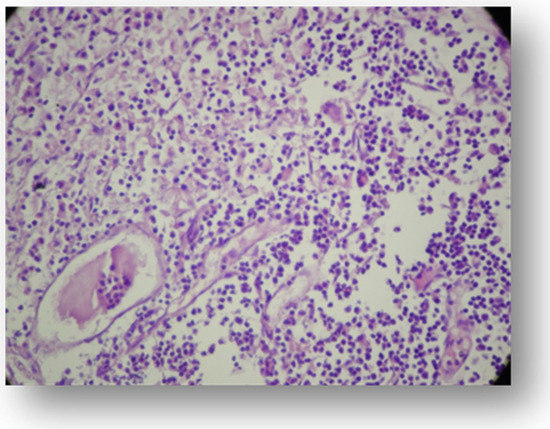

- Vibhute, N.K.; Anikhet, H.V.; Rajendra, T.D.; Puja, P.B.; Aditi, M. Hard facts about stones: Pulpal calcifications: A review. J. Pat. Care 2016, 2, 105. [Google Scholar] [CrossRef]

- Inagaki, Y.; Yoshida, K.; Ohba, H.; Seto, H.; Kido, J.-I.; Haneji, T.; Nagata, T. High Glucose Levels Increase Osteopontin Production and Pathologic Calcification in Rat Dental Pulp Tissues. J. Endod. 2010, 36, 1014–1020. [Google Scholar] [CrossRef]

- Moraru, A.I.; Gheorghiţă, L.M.; Dascălu, I.T.; Bătăiosu, M.; Manolea, H.O.; Forna, D.A.; Râcă, A.M.; Raţiu, C.A.; Diaconu, O.A. Histological and immunohistochemical study on the dental pulp of patients with diabetes mellitus. Rom. J. Morphol. Embryol. = Rev. Roum. Morphol. Embryol. 2017, 58, 493–499. [Google Scholar]

- Shetty, P.; Mulay, S.; Singh, M.; Singh, M.; Reddy, M.; Chawla, M.; Shaikh, M. Histological changes in dental pulp of diabetes mellitus (type II). Int. J. Curr. Res. 2017, 9, 57815–57818. [Google Scholar]